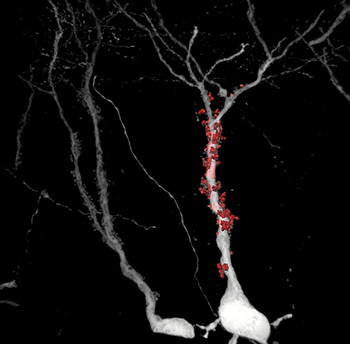

Neurony jsou označeny virovým vektorem, který se v buňkách exprimuje jako intenzivní fluorescenční protein, ten poté vyplní veškeré neuronové výběžky včetně velmi dlouhých axonů. Takto připravené vzorky jsou snímány pomocí konfokálního mikroskopu a posléze analyzovány. Pomocí dedikovaného softwaru je vytvořen 3D model celých dendritů, dendritických trnů a synapsí. Tyto modely jsou posléze použity pro kvantifikaci klíčových anatomických parametrů.

Oproti většině konvenčním přístupům, lze pomocí "Haberlovy metody" studovat neurony fyziologicky starších modelových organismů. To umožnilo vědcům rekonstruovat jemné morfologické detaily myšího mozku staršího jedince s indukovanou Alzheimerovou chorobou. Tato metoda přináší nové možnosti výzkumu této rozšířené neurodegenerativní nemoci.